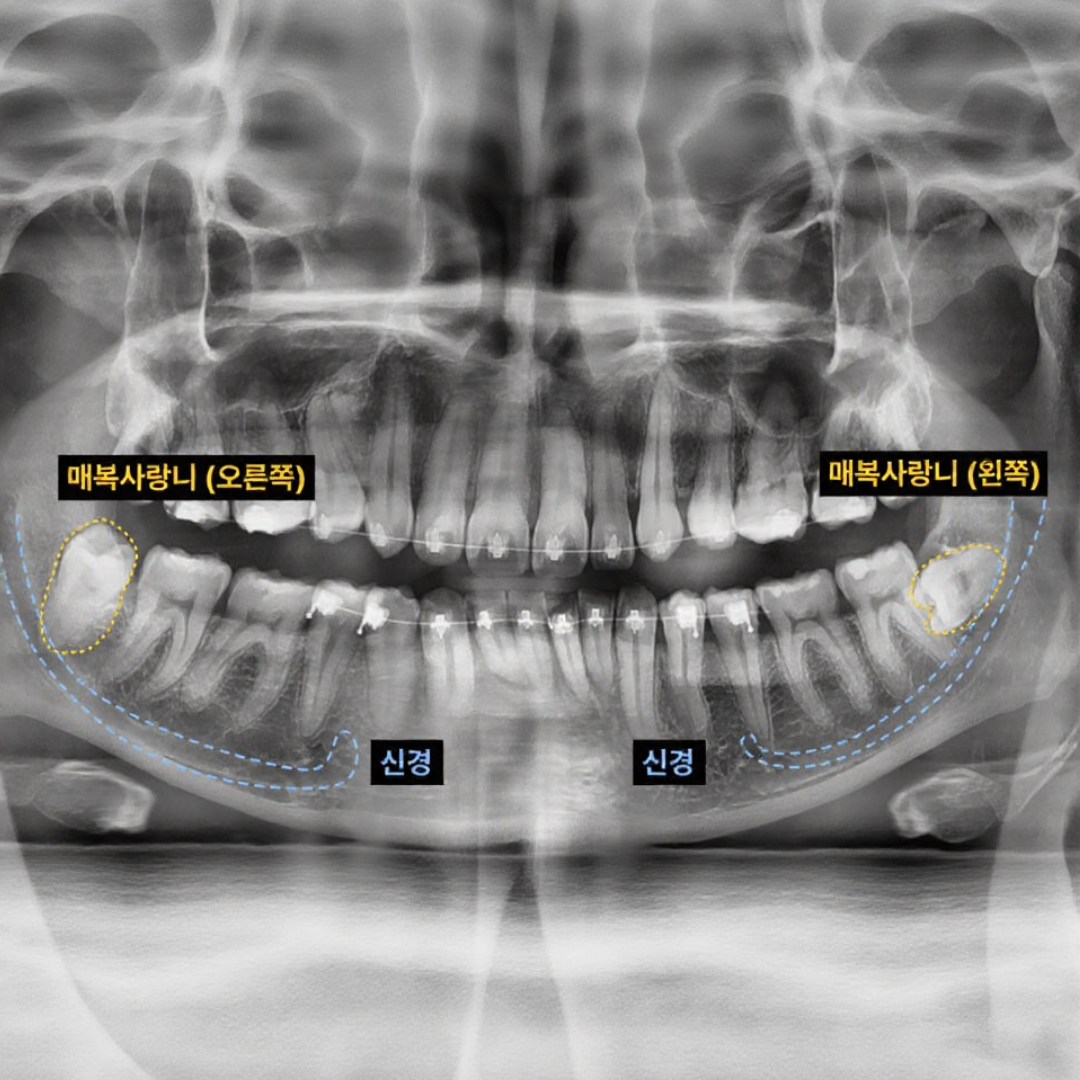

사랑니 발치

• 턱관절 물리치료기

턱관절 장애, 임플란트, 사랑니 발치 시

세포재생, 통증감소 및 염증완화에 효과적​